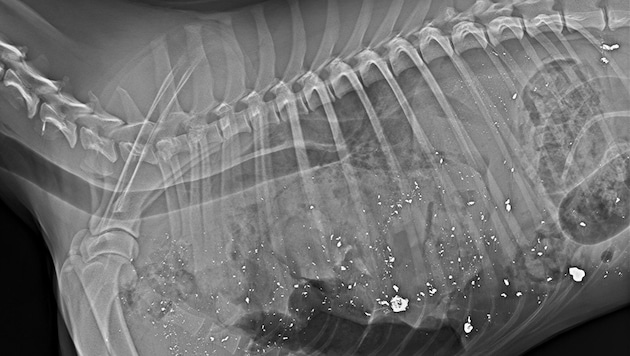

„Habe Röntgen-Beweis, dass Jäger Unwahrheit sagt“

Der Besitzer (30) des in Oberösterreich erschossenen Border Collies „Cooper“ widerspricht nun den Angaben des Todesschützen (84). Die Grünen habe zu dem Fall eine aktuelle Landtagsanfrage an die Jagdlandesrätin (VP) eingebracht.

Der vierjährige Border Collie „Cooper“ ist tot – erschossen von einem Jäger, der ihn am 27. Dezember auf einem Forstweg in Pettenbach im Traunviertel mit einem Fuchs verwechselt haben soll. Angeblich bemerkte der 84-Jährige vom Hochstand aus „ein Tier mit buschiger Lunte“, das der Fährte eines Rehs folgte.